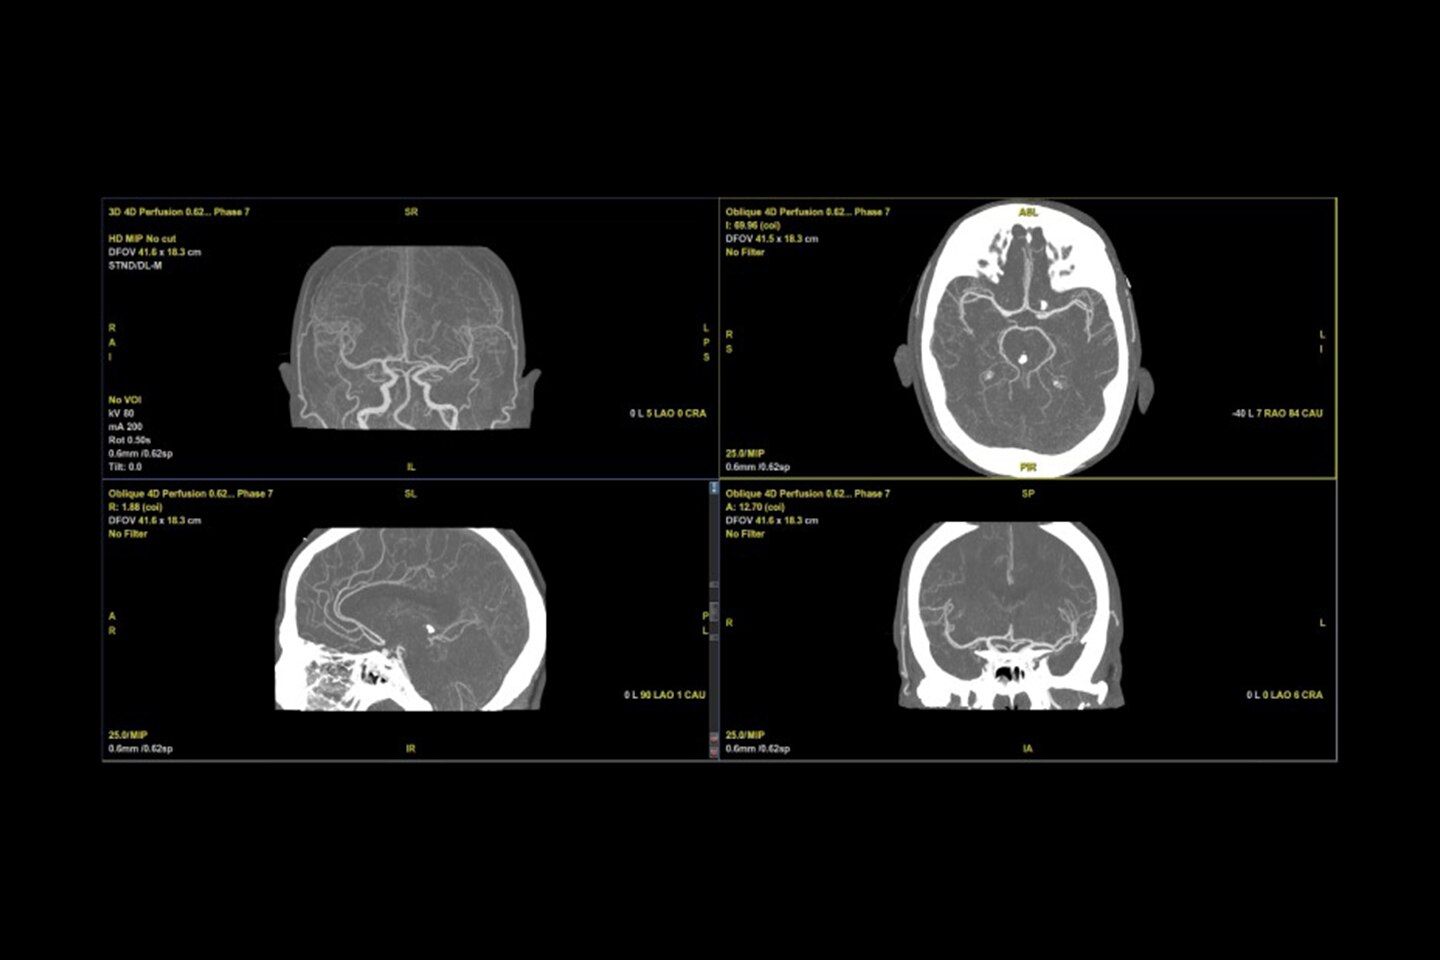

Advanced flow modes: Drive diagnostic confidence in multiple applications, including Microvascular Imaging (MVI) with Radiantflow™ and B-Flow.

Robust advanced quantification tools: 2D Shear Wave Elastography, UGAP, CEUS, and Fusion Imaging enhance precision and speed.